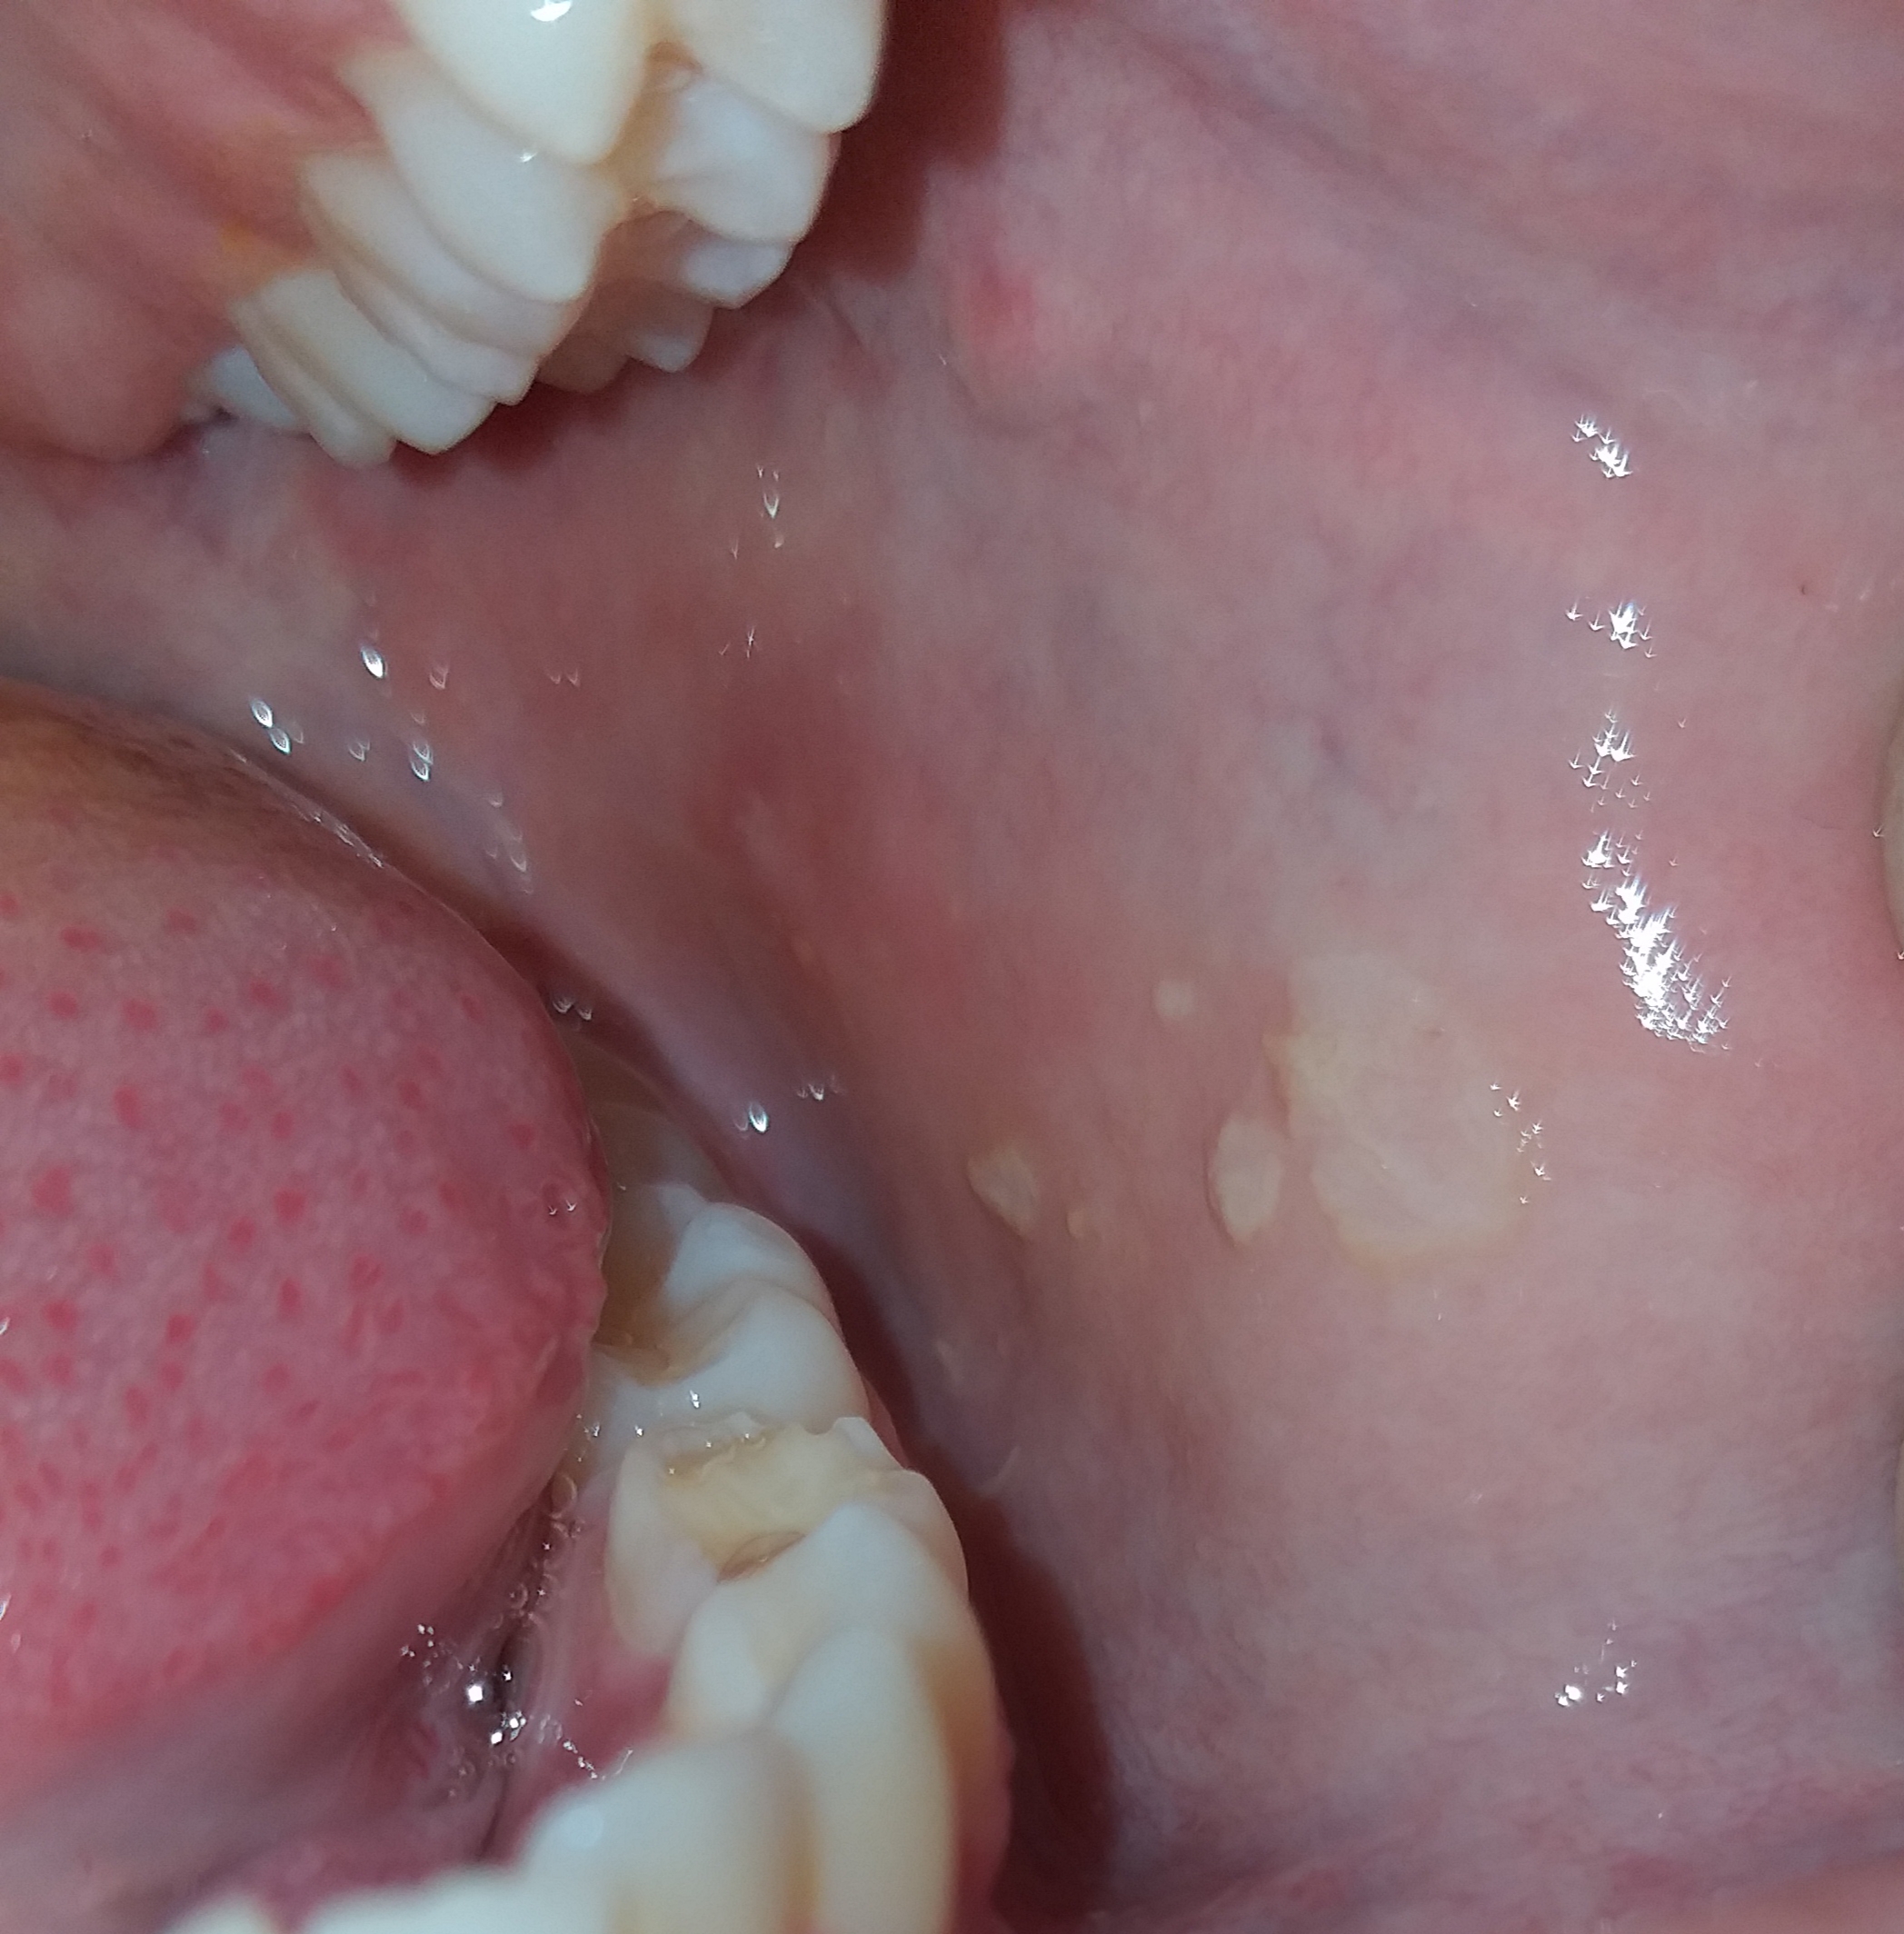

He notado que recurrentemente me han salido ciertas lesiones en la parte interna de las mejillas, son lesiones blancas como se puede ver en las fotos y éstas las puedo quitar fácilmente raspandomelas pero no me genera ningún tipo de dolor ni irritación a la hora de comer alimentos ácidos o después de retirarlas. Cabe destacar que yo tengo la mordida algo irregular y estas lesiones me aparezcan por la friccion, ya que solo me aparecen en la parte interna de la mejilla sobre todo en el lado izquierdo, pero ayer ví que me salieron también algunos puntitos blancos en la encía. En mi lengua no he notado nada raro hasta ahora.

Adjunto las imágenes para que puedan analizar mejor el tipo de lesión que refiero. Esto me tiene preocupado.